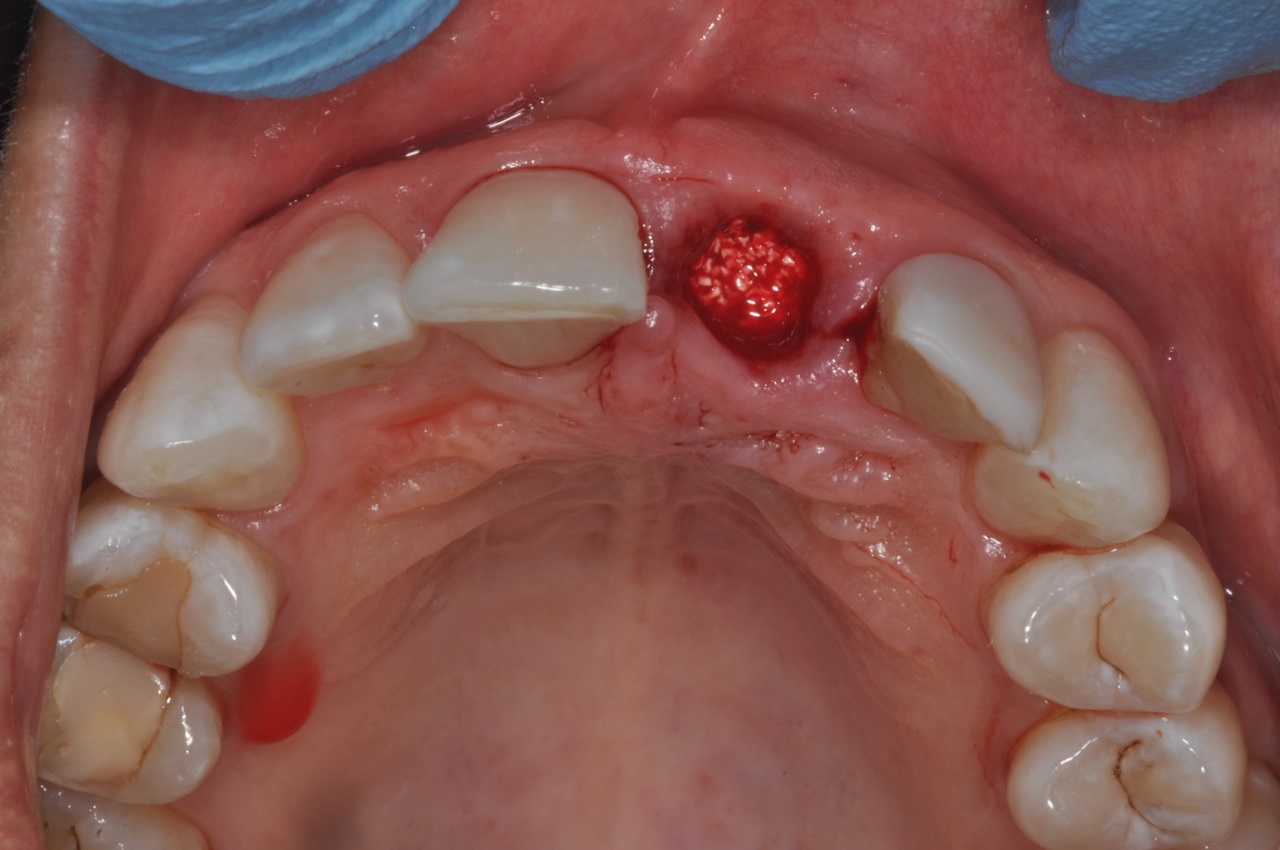

05/16 - Filling of extraction socket with cerabone®

Socket preservation with cerabone® - Dr. R. A. Nader